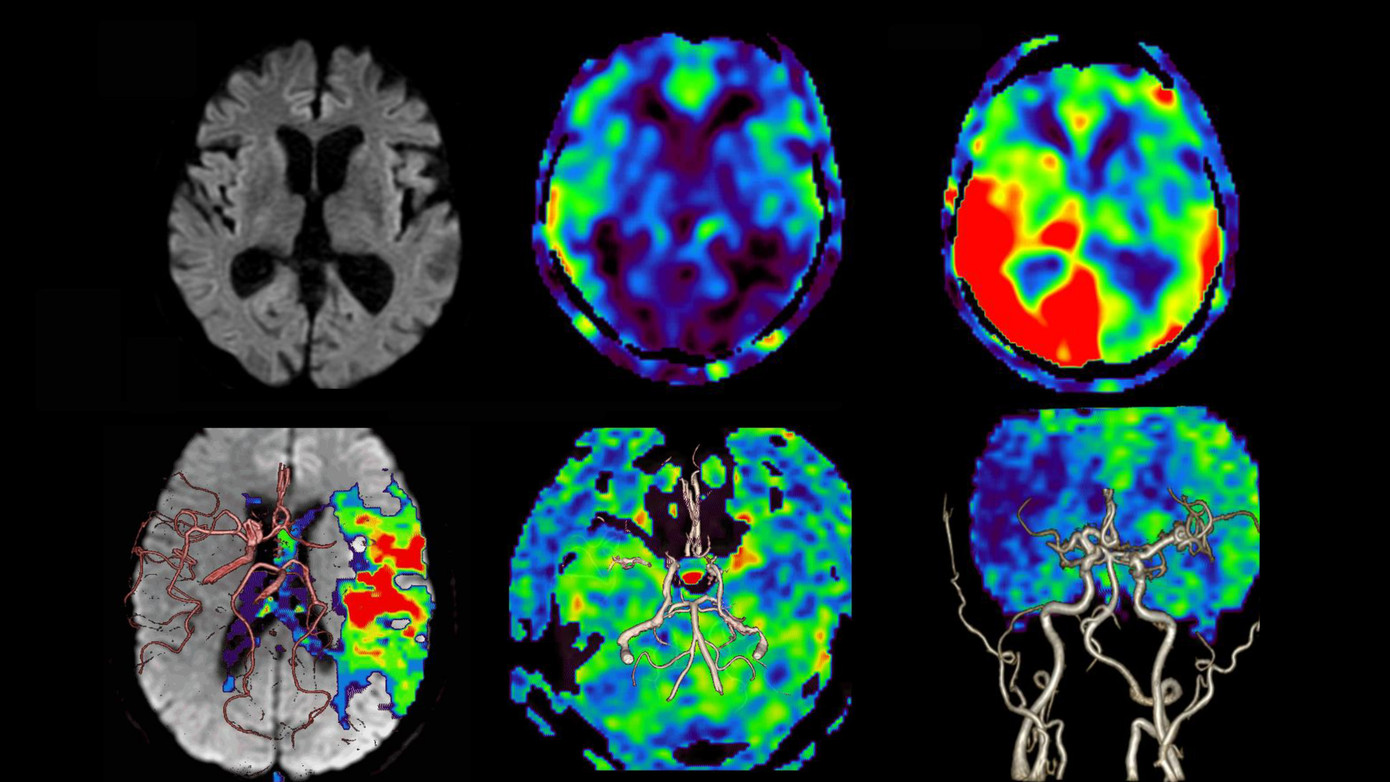

| Hình ảnh chụp cộng hưởng từ tưới máu não không sử dụng thuốc tương phản (MRI não) |